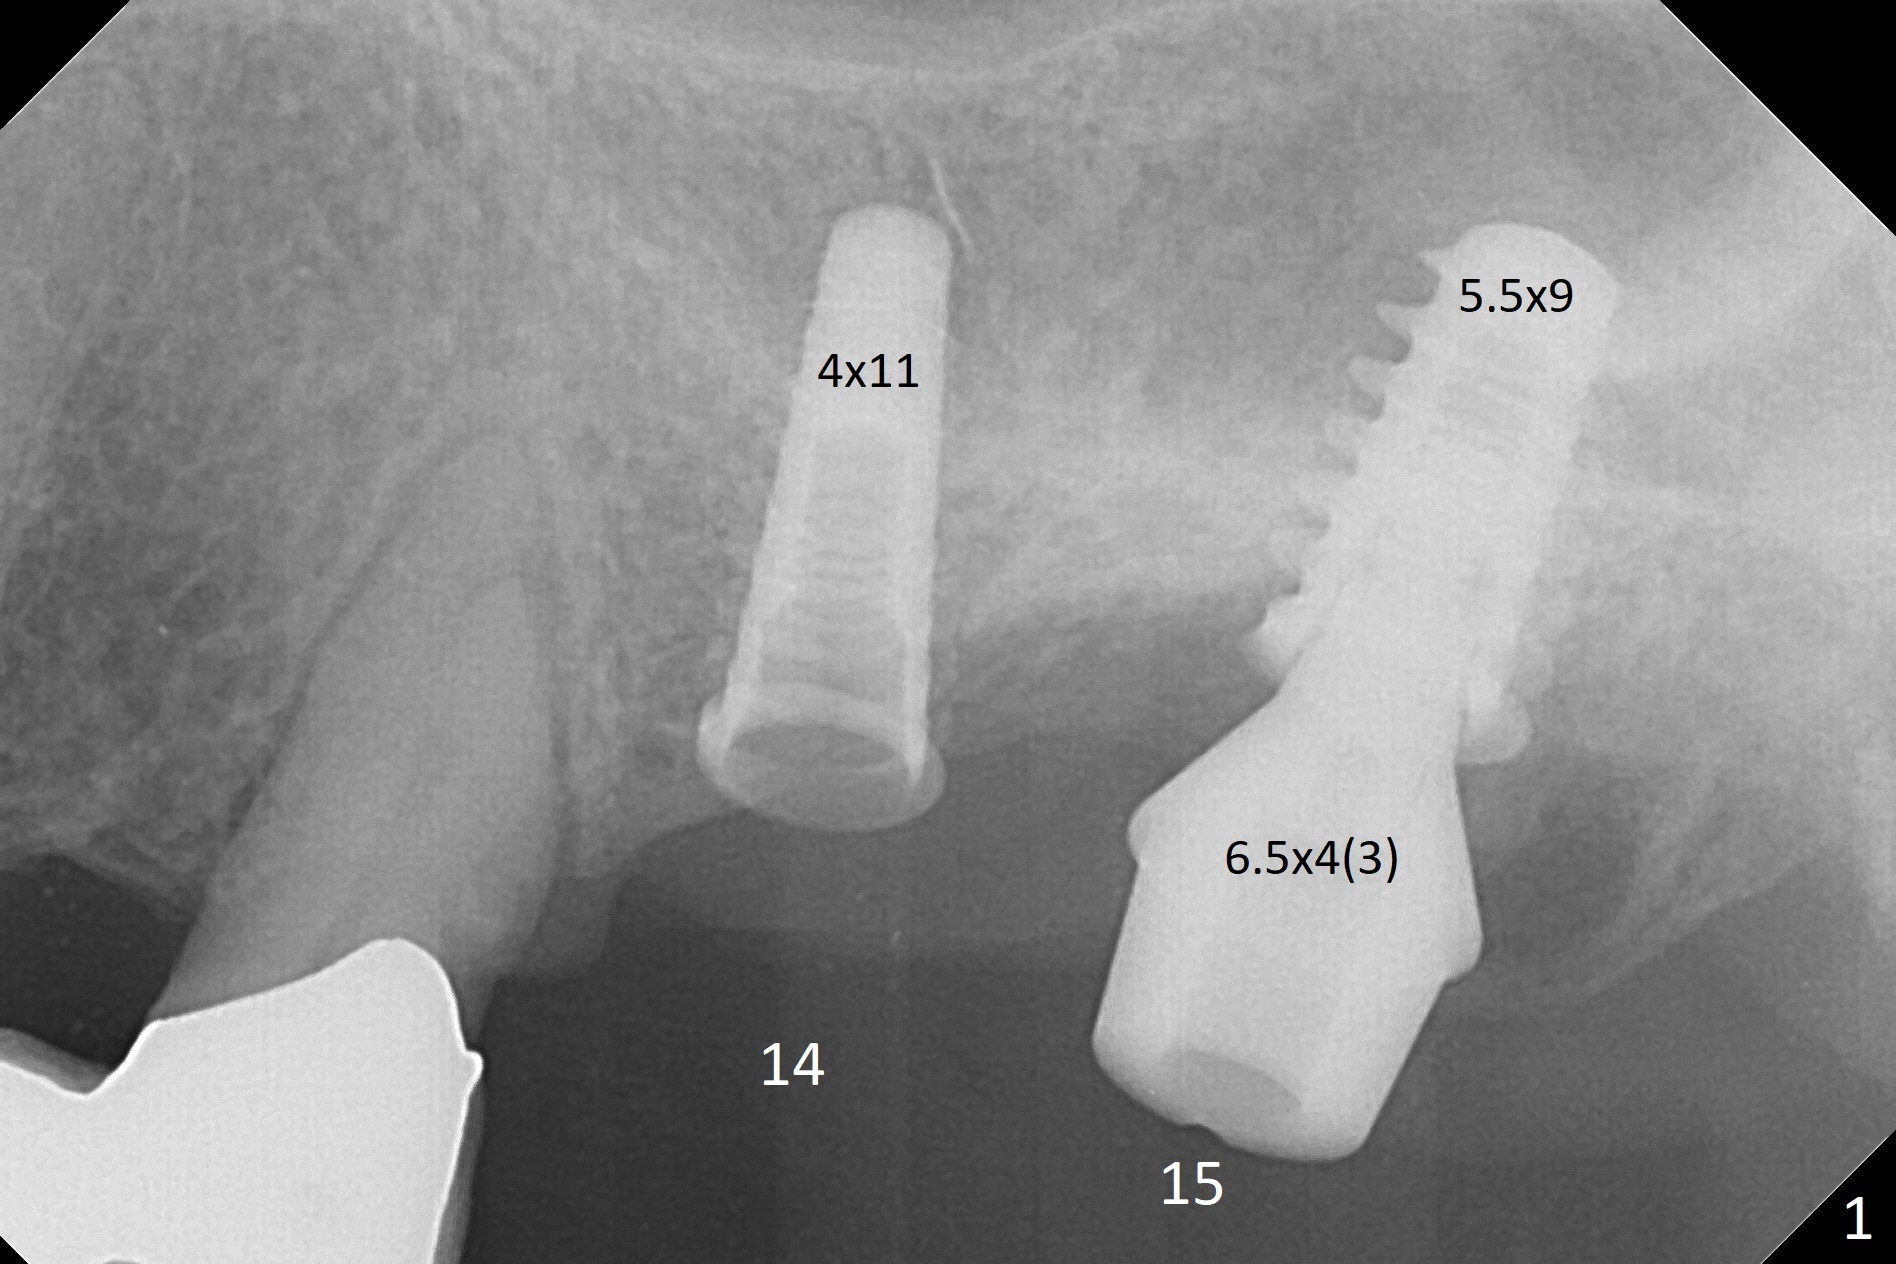

Due to irregular shape of freshly extracted socket at #15, control of depth is difficult. The sinus membrane is perforated after use of bone spreader, probably associated with drills longer than expected. SM taps (5.0 and 5.3 mm) do not achieve stability. When a 5.5x9 mm IBS dummy implant is inserted, initial stability is obtained (Fig.1). Osteotomy at the edentulous area of #14 is uneventful with insertion of a 4x11 mm dummy implant (without involving the sinus floor apparently clinically as well, Fig.1). After adjustment of trajectory, a 4x11 mm definitive implant is placed at #14 with ~ 35 Ncm, while a 6x9 mm implant is placed at #15 with ~35 Ncm (Fig.2 (*: Vanilla Graft with Osteogen)). Periodontal dressing is applied around the abutments and neighboring teeth. There is mild oral and nasal hemorrhage postop. In fact the patient has history of stroke with oral Plavix intake. The medicine stops 4 days preop and is advised to resume after hemostasis is achieved. The patient returns 3 months postop (Fig.3). After changing abutments to 5.5x5.7(3) mm, impression is taken. The crown/abutment at #14 is loose 1 year 10 months post cementation. After use of 5.5 mm profile drill, the crown/abutment is reseated, but the seating is incomplete (Fig.4 <) because of contact of the abutment with the mesial crest (*). A larger profile drill does not help (Fig.5). When a narrower abutment (4.5x7.5(3) mm) is torqued, it appears to be completely seated (Fig.6). After distal surface adjustment of the abutment, impression is re-taken. There are 3 other unfavorable conditions: poor crown/implant ratio and trajectory and #18 missing. The abutment at #14 must have been prepared for parallelism before impression. Return to Upper Molar Immediate Implant, Prevent Molar Periimplantitis (Protocols, Table), Armaments No Deviation Prevent Screw Loosening Xin Wei, DDS, PhD, MS 1st edition 11/28/2017, last revision 02/23/2021